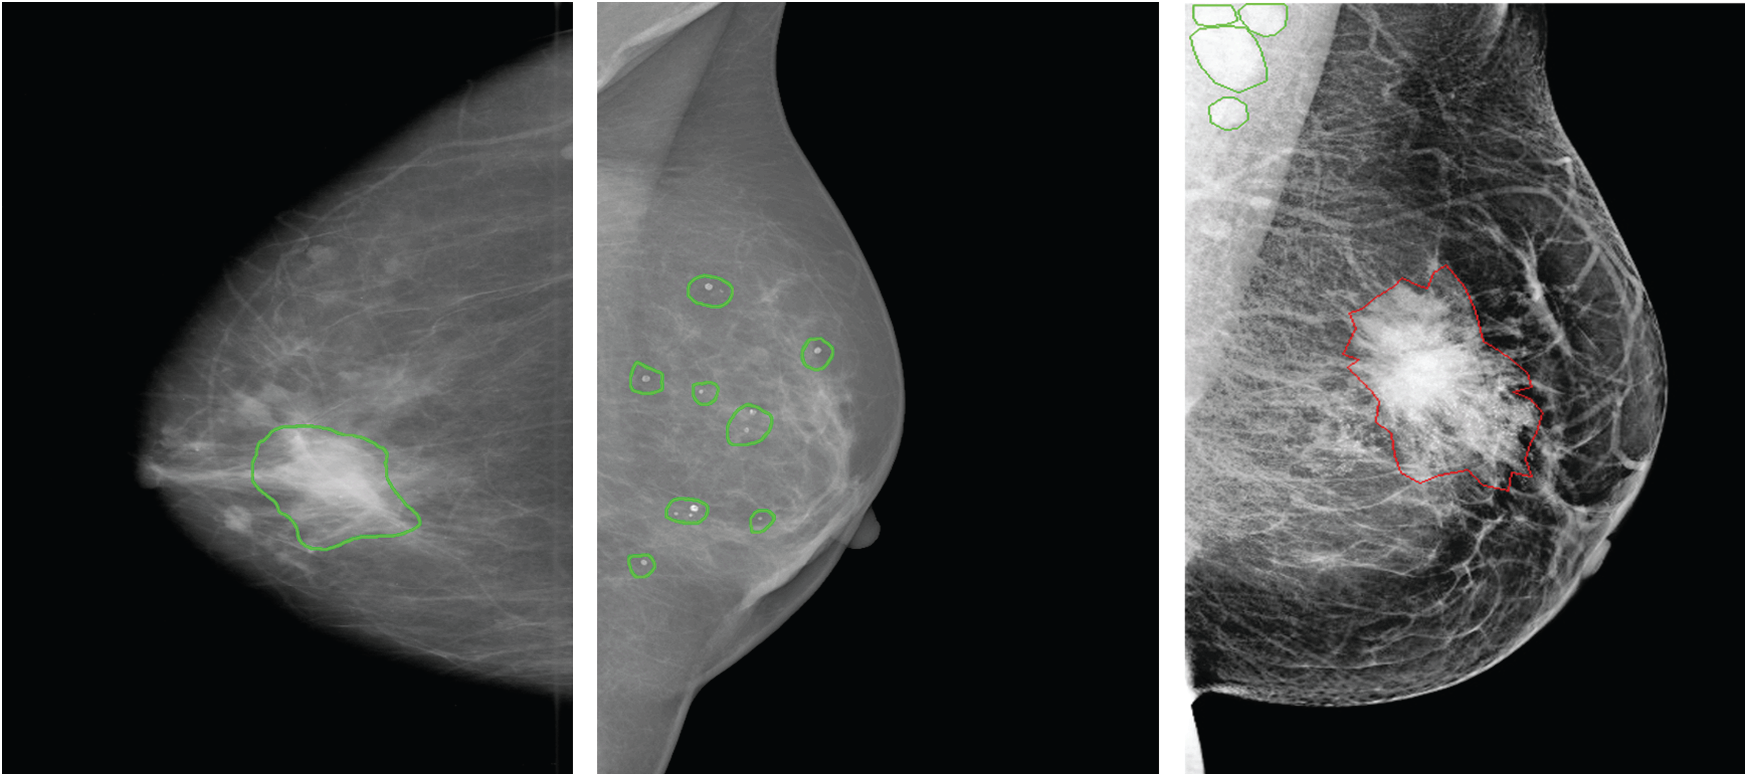

Accordingly, results in Tab. 2 show the clear ability of the YOLO-based model to better detect and classify the mass lesions from the entire mammograms than the calcification lesions. This is aligned with the difference between the two types of lesions in terms of shape, size and texture. In fact, calcifications are often small and randomly distributed in challenging positions within the breast [66]. As shown in Fig. 5, calcifications do not have standard shape and they can be bilateral, thick linear, clustered, pleomorphic and vascular, etc. These varied shapes can limit the detection and classification for this type of lesions and yield more failed cases than for the other lesions. Below in Fig. 5, it shows a case of a coarse-like calcification that has crossed thick lines with irregular size (image on the left, taken from the CBIS-DDSM dataset). Another case shows pleomorphic calcifications that have randomly distribution (image on the middle, taken from the INbreast dataset). In addition, example of clustered calcifications located on the pectoral muscle that presents a challenging case in mammography (image on the right, taken from the Private dataset).

Figure 5: Examples of different calcifications shape and localization (ground-truth of calcification is marked in green, ground-truth of mass is marked in red) for CBIS-DDSM, INbreast and private datasets (from left to right)